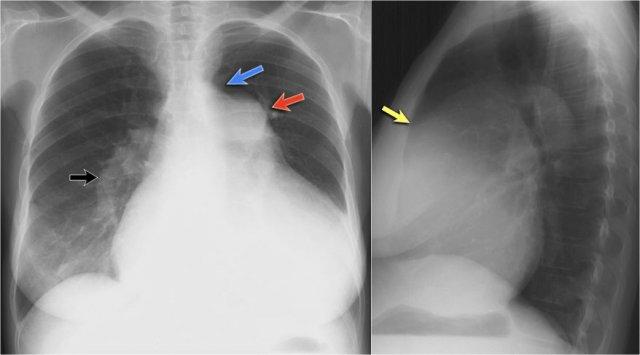

Trên phim X-quang ngực tư thế nghiêng, các bờ tim cần được xác định rõ ràng, và tĩnh mạch chủ dưới (IVC) thường có thể thấy đổ vào nhĩ phải.

Khoang sau xương ức bình thường chứa phổi có khí và do đó phải có hình ảnh thấu quang (tối trên phim), kéo dài xuống dưới đến mức thất phải tiếp xúc với xương ức (mũi tên đen nhỏ).

Dấu hiệu cột sống

Khi đánh giá các thân đốt sống trên tư thế nghiêng, chúng phải có hình ảnh thấu quang (tối hơn) tăng dần từ trên xuống dưới do lượng phổi có khí chồng lên ngày càng nhiều (mũi tên trắng).

Nếu các đốt sống ngực dưới có hình ảnh đậm bất thường, điều này có thể gợi ý bệnh lý ở các thùy dưới, chẳng hạn như đông đặc hoặc khối — đây được gọi là dấu hiệu cột sống.

Đánh giá Cơ hoành

- Vòm hoành phải phải được nhìn thấy rõ ràng ở phía trước đến tận thành ngực (mũi tên đỏ), thể hiện ranh giới giữa phổi có khí và mô mềm ổ bụng.

- Vòm hoành trái thường chỉ nhìn thấy đến điểm tiếp giáp với bóng tim (mũi tên xanh lam), phía ngoài điểm đó ranh giới bị mất do tỷ trọng tương đương giữa tim và các tạng bụng phía trên.